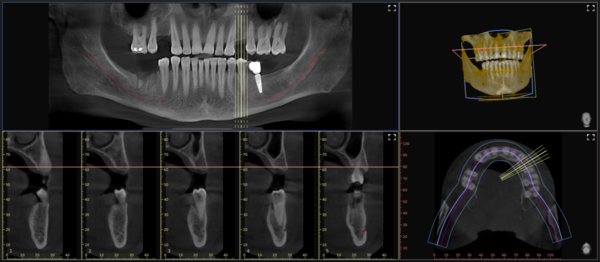

Il software VistaSoft, in sinergia con la CBCT VistaVox S, appena eseguito un esame volumetrico, ricostruisce una vista Panorex perfettamente a fuoco su due linee distinte, una per le radici e le corone, e l’altra per il profilo osseo (esclusiva Dürr Dental), permettendo al clinico di analizzare subito la corretta visualizzazione del caso. Inoltre, sempre tramite l’algoritmo della rete neurale, traccia il decorso del nervo alveolare inferiore, con un livello di precisione superiore al 98%. Al clinico non resta che verificare l’operato dell’intelligenza artificiale e dedicare il suo prezioso tempo all’analisi del caso e alla risoluzione del quesito diagnostico.